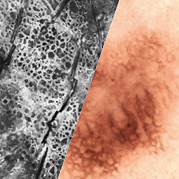

Development and sale of the world's first in vivo confocal laser scanning microscope (CLSM) VivaScope. For the first time, an optical biopsy in real time is possible.

All images courtesy of Prof. Dr Elke Sattler, Dr Martina Ulrich, Prof. Dr Julia Welzel

H&E-like images during surgery. Within minutes. Immediate results possible.